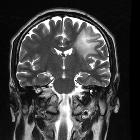

MRI

The International Magnetic Resonance Imaging in MS Collaboration categorizes the different MRI appearances of tumefactive demyelination:

- ring-enhancing

- diffusely infiltrative

- megacystic

- Balo-like

Tumefactive demyelinating lesions tend to be large but with relatively little mass effect or surrounding edema. Centrally located dilated veins have also been observed within these lesions .